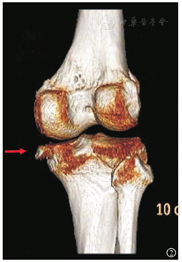

病例2 患者男,50岁,因"摔伤致右膝关节疼痛3 d"于2019年2月入院。入院查体:右膝关节肿胀压痛,活动受限,肢端血供感觉正常。入院查右膝CT(图5)及MRI(图6)提示右膝后交叉韧带止点无移位骨折,胫骨平台内后缘撕脱骨折累及内侧副韧带深层,诊断"反式Segond骨折"。完善术前准备后行右膝关节镜手术,麻醉下查体示右膝关节肿胀,前后抽屉及Lachman试验阴性,内外翻试验阴性。术中清理血肿后探查前后交叉韧带完整,后叉止点骨折无移位,发现内侧半月板后角撕裂行内侧半月板成形,内侧撕脱骨折块位于内侧半月板下方并翻转,细针定位骨折块位置后取膝关节内侧3 cm切口,分离至骨折部位,见骨折块菲薄约1 cm×0.5 cm×0.3 cm,连及内侧副韧带深层,考虑骨块太小空心钉固定困难改用缝线捆扎,复位后在关节镜监视下在骨折块前外及后外建立2 mm骨隧道,用硬膜外导针过线,将2号爱惜绑线捆扎复位骨折块,平台内侧放置小T型钢板作为阻挡支撑,将爱惜绑线打结在钢板上,术中关节镜探查骨折解剖复位(图7,图8,图9,图10)。术后复查CT进一步证实示骨折解剖复位(图11)。术后常规佩戴可调节膝关节支具伸直位固定并行直腿抬高锻炼股四头肌,术后2周开始膝关节0°~90°屈曲活动,术后6周膝关节0°~120°屈曲活动并拄双拐保护下开始部分负重,术后10周膝关节完全负重并达到正常活动度。术后半年复查,患者右膝无疼痛,能慢跑,Lysholm评分95分。

反式Segond骨折位于胫骨平台的内缘,因此在标准的膝关节X线正侧位片上容易漏诊,而斜位X线片上可以更好地显示该骨折。由于此类骨折常常合并膝关节韧带、半月板损伤,所以需要CT、MRI等影像检查进一步评估其他伴随软组织损伤,一旦漏诊可能会对治疗效果产生不利影响。